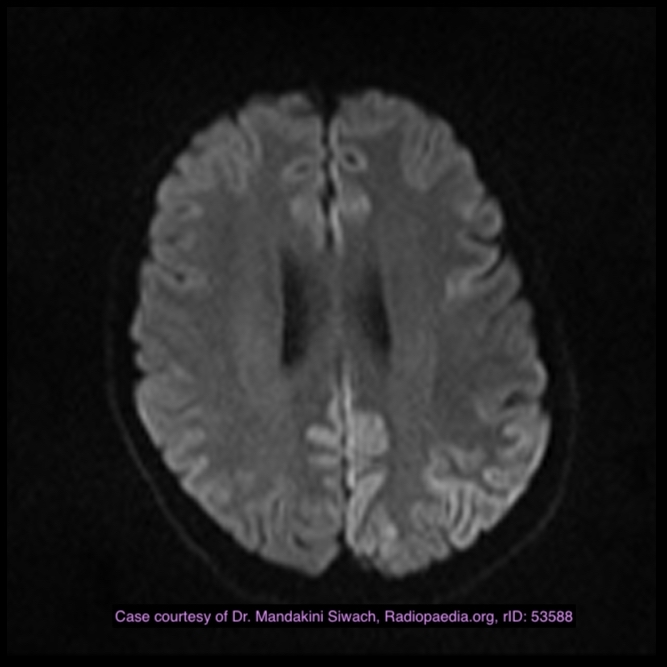

Cerebral fat embolism

Note the multiple sites of oedema and haemorrhage, involving the brain stem and corpus callosum as well as subcortical white matter and left cerebral peduncle. High FLAIR signal is also seen in the dorsal midbrain. EVD insitu.

Case Discussion

Diffuse axonal injury can be subtle on CT but have devastating consequences for the patient. This is a case of grade III injury (involvement of brainstem) and carries a poor prognosis.

Diffuse axonal injury

Dr Jay Gajera◉ and Assoc Prof Frank Gaillard◉◈ et al.

Diffuse axonal injury (DAI), also known as traumatic axonal injury (TAI), is a severe form of traumatic brain injury due to shearing forces. It is a potentially difficult diagnosis to make on imaging alone, especially on CT as the finding can be subtle, however, it has the potential to result in severe neurological impairment.

The diagnosis is best made on MRI where it is characterised by several small regions of susceptibility artifact at the grey-white matter junction, in the corpus callosum, and in more severe cases in the brainstem, surrounded by FLAIR hyperintensity.

Radiographic features

Diffuse axonal injury is characterised by multiple focal lesions with a characteristic distribution: typically located at the grey-white matter junction, in the corpus callosum and in more severe cases in the brainstem (see: grading of diffuse axonal injury).

MRI

MRI is the modality of choice for assessing suspected diffuse axonal injury even in patients with entirely normal CT of the brain 5,6. MRI, especially SWI or GRE sequences, exquisitely sensitive to paramagnetic blood products may demonstrate small regions of susceptibility artefact at the grey-white matter junction, in the corpus callosum or the brain stem. Some lesions may be entirely non-haemorrhagic (even using high field strength SWI sequences). These will, however, be visible as regions of high FLAIR signal.